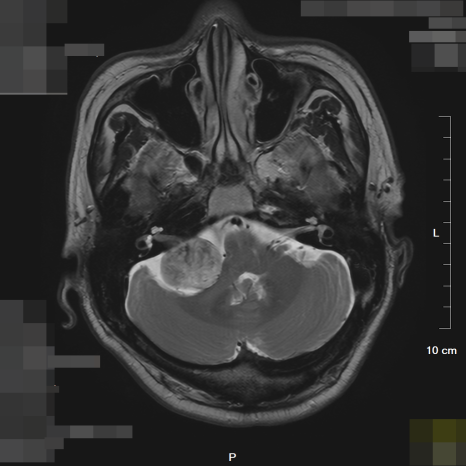

(좌) 3cm크기의 종괴 소견 뇌MRI / (우) 정상 소견의 뇌MRI

정밀 뇌 MRI 검사 결과, 환자분의 소뇌를 강력하게 누르고 있는 약 3cm 크기의 종괴(종양)가 확인되었습니다. 2년 동안 환자분을 괴롭혔던 그 어지럼증은 몸이 약해서가 아니라, 뇌 속에서 자라나는 종양이 보내는 균형 감각 상실의 경고였던 것입니다.